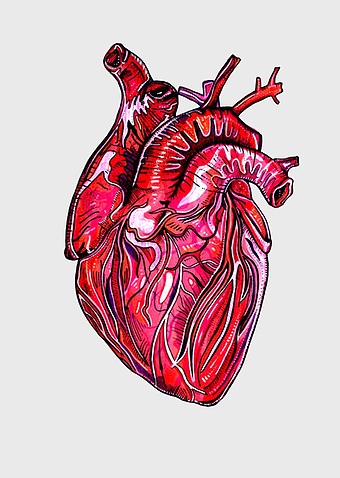

- heart and lung anatomy

Heart Anatomy Diagram, human heart drawing, realistic heart illustration, cardiovascular system, medical illustration, organ structure, human anatomy study -

human heart anatomy, cardiovascular system illustration, medical heart diagram, heart organ structure, human body organ visuals, anatomical heart drawing, heart health -

human heart diagram, cardiovascular system anatomy, blood vessel chart, free body diagram, circulatory system illustration, medical organ visualization, human anatomy study -

human heart anatomy, cardiac muscle illustration, circulatory system model, heart health visual, cardiovascular organ diagram, medical heart image, visceral structure depiction -

human heart anatomy, red heart illustration, heart organ diagram, heart muscles and valves, cardiovascular system diagram, human body organ chart, anatomical heart structure -

heart anatomy diagram, human heart ventricle, human body physiology, heart beat animation, cardiovascular system, medical illustration, organ structure analysis -

human heart illustration, cardiac anatomy diagram, heart blood vessels, medical organ visuals, cardiovascular system chart, human anatomy study, circulatory system illustration -

human heart anatomy illustration, watercolor heart painting, heart shape medical care, red heart organ, cardiovascular system diagram, anatomical heart drawing, heart structure analysis -

human heart anatomy, heart science illustration, human body heart diagram, cardiovascular system, cardiac structure, medical heart image, heart health education -

heart anatomy illustration, cardiovascular system diagram, circulatory system medical, vascular system sonography, human body blood flow, arterial network visualization, heart function analysis -

human heart drawing, red line art heart, anatomical heart illustration, heart organ diagram, cardiovascular system sketch, medical heart graphic, heart anatomy chart -

heart anatomy diagram, circulatory system illustration, superior vena cava label, inferior vena cava structure, cardiovascular system chart, human heart ventricles, medical education graphics -

human heart anatomy, American Heart Association drawing, red blood vessel illustration, fictional character heart, cardiovascular system diagram, medical art illustration, organ structure depiction -